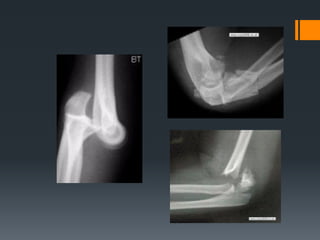

Elbow region

Layers of the elbow

Bone

1 humerus

2 radius

3 ulna